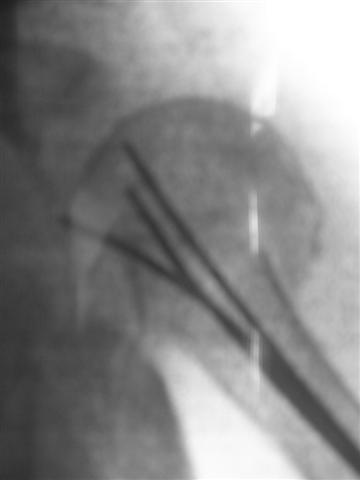

Another option could be closed nailing, see an example, the surgery was done 2 days ago. In common such surgeries are performed under regional anesthesia, not general.

One more option can be fixation by V-shape stressed wires.

Pls compare wound size visible at x-rays of your example with ones after typical closed nailing of the proximal humerus.